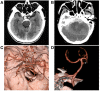

Perimesencephalic nonaneurysmal subarachnoid hemorrhage (PNSAH) is a distinctive disease, representing SAH centered in perimesencephalic cisterns, with negative angiography findings. In recent years, the number of patients with PNSAH has increased significantly; however, the knowledge of PNSAH is insufficient. Therefore, we performed a review of the literature from a PubMed search and recounted our understanding of PNSAH. In this review, we summarized that current high-resolution computed tomography angiography is an acceptable replacement for digital subtraction angiography to rule out aneurysms in PNSAH with strict criteria. The current hypothesis about the etiology of PNSAH is that there is deep vein rupture from aberrant venous anatomy and increased intracranial venous pressure. PNSAH is associated with mild symptoms and lower rates of hydrocephalus and symptomatic vasospasm. For PNSAH, conservative treatment has been the mainstream treatment. PNSAH has a benign clinical course and an excellent prognosis; in long-term follow-up, re-bleeding and death were uncommon.